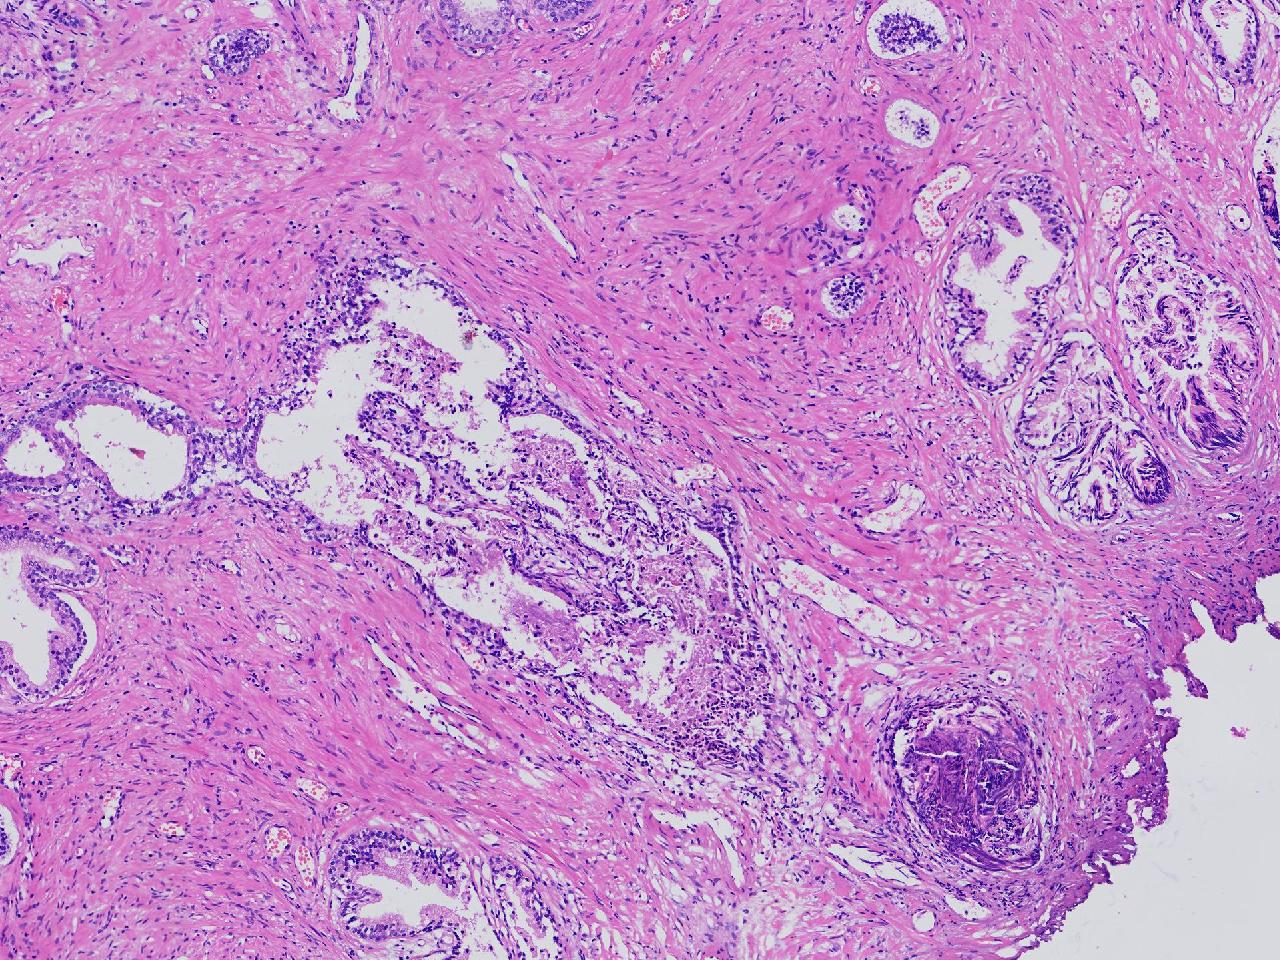

男,68岁,前列腺电切标本。

前列腺电切标本

灰粉色条索状软组织多块,5X4X3厘米。

前列腺增生。

BPH.